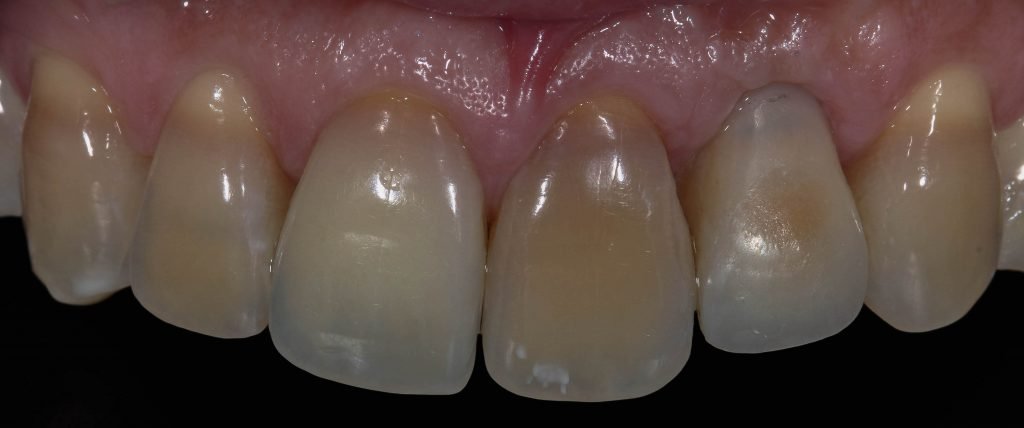

Punto Bajío Casos Clínicos Prótesis Fija sobre Implante unitario Inicio Provisional Final Prótesis Parcial Fija sobre 2 Implantes 2 Implantes Final Prótesis Bucal Removible Inicial Inicial Superior Inicial Inferior Rayos X Inicial Rayos X Inicial Frontal Final Final Superior Final Inferior Prótesis Parcial Fija/ Coronas de Circonio Sonrisa Inicial Foto Inicial Foto Inicial Inferior Foto Final Inferior Foto Final Sonrisa Final Prótesis Total Protesis Inmediatas 1 Protesis Inmediatas 2 Prótesis Removible/ Coronas Metal-Ceramica Carillas Incrustaciones Endodoncia